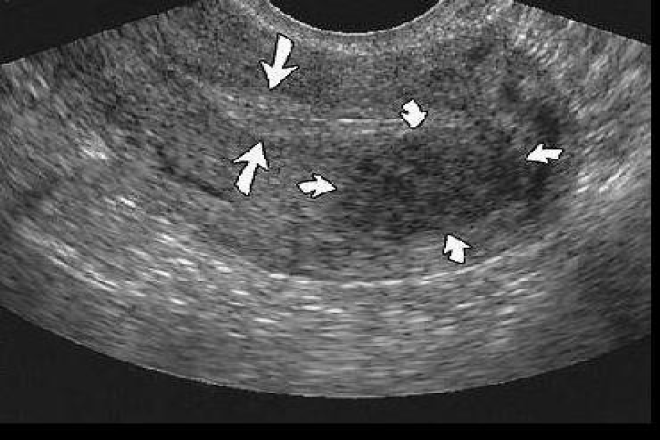

Los ovarios son órganos pares ovalados que miden aproximadamente 3x2x2 cm y pesan 3-4g aproximadamente. son asimétricos, generalmente el derecho es más grande.  Se encuentran en la superficie posterior del ligamento ancho. No están cubiertos por peritoneo, sino por una capa de epitelio germinal. Tienen una capa externa dura de túnica albugínea  por debajo de la capa germinal. La superficie anterior del ovario se inserta a la superficie posterior del ligamento ancho por un corto mesoovario que se fusiona con la superficie ovárica. El polo inferior del ovario se inserta en el útero por el ligamento ovárico.